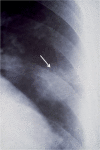

Dirofilariasis represents a zoonotic mosaic, which includes two main filarial species (Dirofilaria immitis and D. repens) that have adapted to canine, feline, and human hosts with distinct biological and clinical implications. At the same time, both D. immitis and D. repens are themselves hosts to symbiotic bacteria of the genus Wolbachia, the study of which has resulted in a profound shift in the understanding of filarial biology, the mechanisms of the pathologies that they produce in their hosts, and issues related to dirofilariasis treatment. Moreover, because dirofilariasis is a vector-borne transmitted disease, their distribution and infection rates have undergone significant modifications influenced by global climate change. Despite advances in our knowledge of D. immitis and D. repens and the pathologies that they inflict on different hosts, there are still many unknown aspects of dirofilariasis. This review is focused on human and animal dirofilariasis, including the basic morphology, biology, protein composition, and metabolism of Dirofilaria species; the climate and human behavioral factors that influence distribution dynamics; the disease pathology; the host-parasite relationship; the mechanisms involved in parasite survival; the immune response and pathogenesis; and the clinical management of human and animal infections.